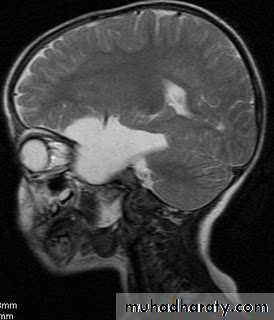

Suprasellar Arachnoid Cyst

Investigations:

CT Brain

MRI Brain